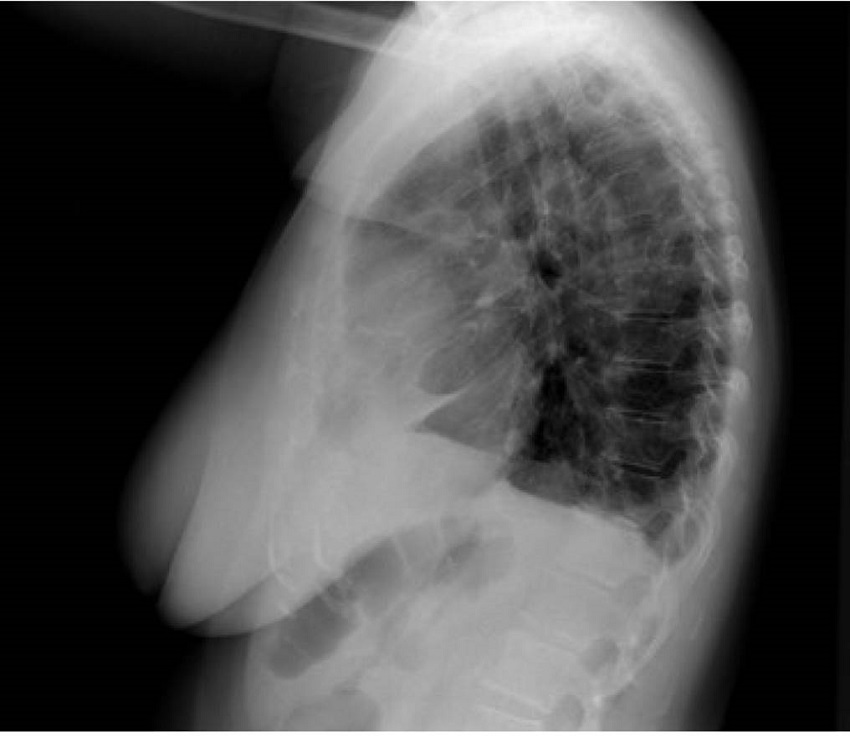

En urgencias hospitalarias, el estudio se completó con una prueba de laboratorio, en la que se objetivó un aumento de los reactantes de fase aguda (proteína C reactiva 118,7 mg/L y fibrinógeno 692 mg/ dL), sin aparición de otros hallazgos sugestivos de infección ni elevación de marcadores de daño miocárdico o indicadores de insuficiencia cardíaca. También se le hizo una radiografía de tórax, en la que se apreció una imagen compatible con cardiomegalia versus masa mediastínica anterior, con una pérdida de volumen en lóbulo inferior derecho y derrame pleural bilateral (figuras 1 y 2).